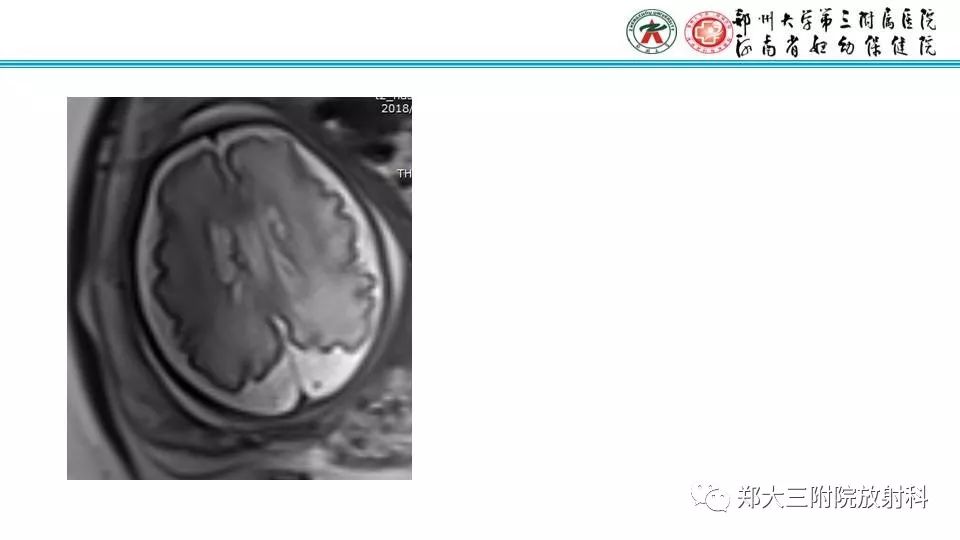

【PPT】室周假性囊肿-2